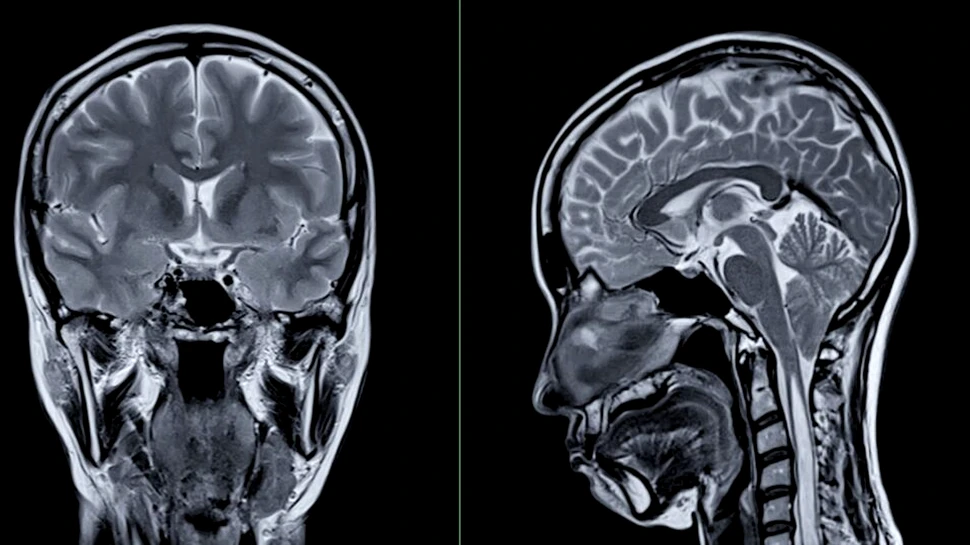

Foto: Shutterstock

Creierul nostru este centrul de comandă al corpului, responsabil pentru memorie, luarea deciziilor și mișcare. Cu toate acestea, multe obiceiuri zilnice afectează în mod silențios creierul și conexiunile sale în timp.